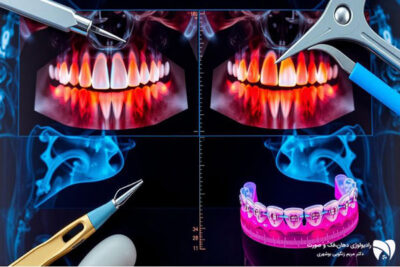

استفاده از تکنیک‌های تصویربرداری سه‌بعدی در برنامه‌ریزی درمان ارتودنسی

تکنیک‌های تصویربرداری سه‌بعدی یا CBCT (Cone Beam Computed Tomography) از جمله پیشرفته‌ترین روش‌های تصویربرداری دندانی است که در ارتودنسی مورد استفاده قرار می‌گیرد. این تکنیک به ارتودنتیست‌ها امکان می‌دهد که تصاویر سه‌بعدی دقیقی از فک، دندان‌ها و ساختارهای اطراف به‌دست آورند. این اطلاعات سه‌بعدی به دندانپزشکان کمک می‌کند تا با دقت بیشتری به برنامه‌ریزی درمان بپردازند و تصمیم‌گیری‌های بالینی بهتری انجام دهند. از جمله مزایای این تکنیک می‌توان به کاهش اشتباهات در قرار دادن دستگاه‌های ارتودنسی و افزایش موفقیت درمان اشاره کرد.

تاثیر دقت بالای رادیوگرافی دیجیتال در بهبود درمان

رادیوگرافی دیجیتال یکی دیگر از نوآوری‌های مهم در زمینه تصویربرداری دندانی است که دقت و سرعت بالاتری نسبت به روش‌های سنتی دارد. این تکنولوژی به دندانپزشکان اجازه می‌دهد که به‌صورت آنی تصاویر دقیقی از دندان‌ها و فک‌ها دریافت کنند و آن‌ها را برای بررسی‌های دقیق‌تر مورد استفاده قرار دهند. دقت بالای این تصاویر باعث می‌شود که حتی کوچک‌ترین ناهنجاری‌ها نیز شناسایی شده و درمان‌های مناسب برای آن‌ها در نظر گرفته شود.